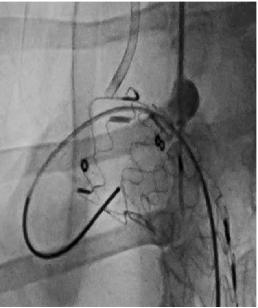

case 3

III型弓合并长段动脉瘤病变,LSA开口位于瘤体且与主动脉弓夹角小,病变累及长度长,手术截瘫风险高。

传统开窗技术因血管成角小、路径迂曲难以精准定位。

通过三开窗技术(LSA+LCCA+其他分支)完成重建,Futhrough系统的高顺应性和行程控制能力有效避免了血管损伤,术后截瘫风险显著降低。